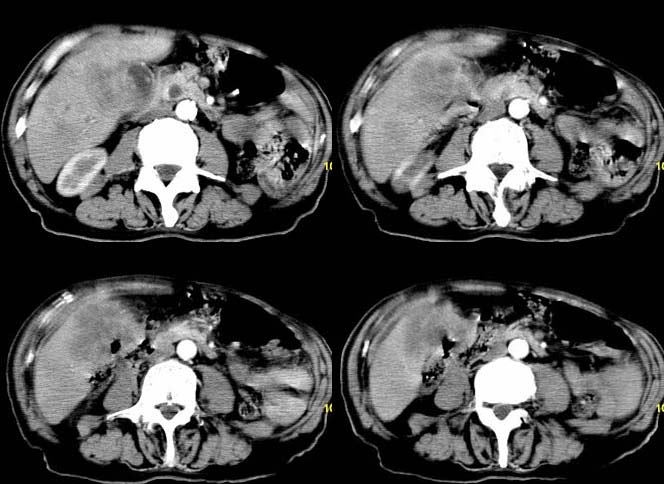

以下是引用余辉在2007-12-6 22:23:00的发言:[br]胆囊内多枚结石影,胆管全程扩张,右肝内病灶强化符合脓肿表现现(左肝病灶图像未传完),考虑急性梗阻性化脓性胆囊胆管炎合并肝多发脓肿(建议补传左肝病灶图像)